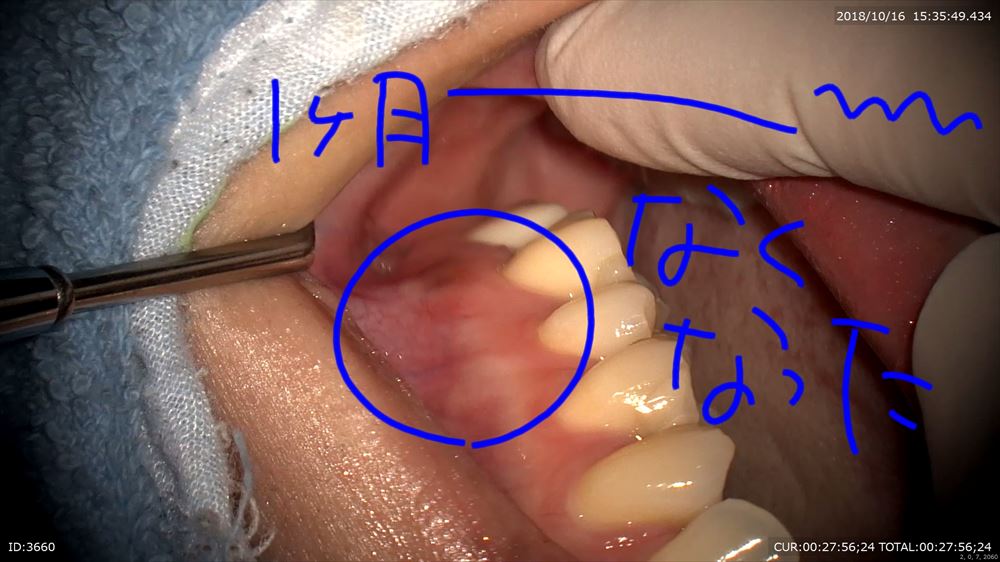

二回目の来院。消えてます。治った。